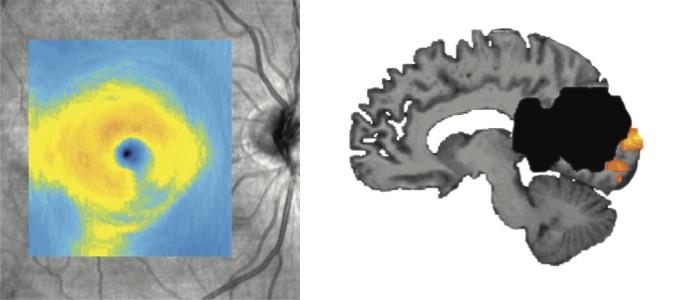

image: The left image shows degeneration that typically occurs in the eye (lower right corner) after a patient has a stroke in the visual processing area of the brain. The area of degeneration corresponds to the location of blind areas of the patient's visual field. Carnegie Mellon and University of Rochester researchers found the eye is less likely to degenerate when the brain continues to respond to visual stimuli despite the patient's blindness from the stroke. The right image shows lesion in black and visual cortex activity to stimuli presented in blind areas of the patient's visual field in orange.

When a stroke occurs in the primary visual cortex, the neurons responsible for processing vision can be damaged. Depending upon the extent of the damage, this can result in blind areas in the field of vision. While some patients spontaneously recover vision over time, for most the loss is permanent. A long-known consequence of damage to neurons in this area of the brain is the progressive atrophy of cells in the eyes, called retinal ganglion cells.

"While the eye is not injured in the stroke, cells in the retina that send projections to parts of the brain that are damaged will degenerate over time," Mahon said. "Once this occurs, it becomes more and more unlikely for vision to recover at that location."

The team found that the survival of the retinal ganglion cells depended upon whether or not the primary visual area of the brain to which they are connected remained active. Eye cells that were connected to areas of visual cortex that were no longer active would atrophy and degenerate, leading to permanent visual impairment.

However, the researchers observed that some cells in the eye remained healthy, even though the patient could not see at the corresponding field of vision. This finding suggests that these eye cells remain connected to unscathed neurons in the visual cortex and that visual information was making its way from the eyes to the visual cortex, even though this information was not being interpreted by the brain in a manner that allowed sight.